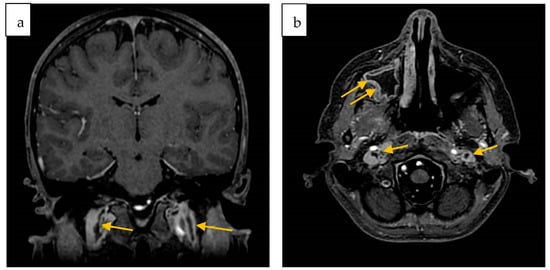

2. Case Report